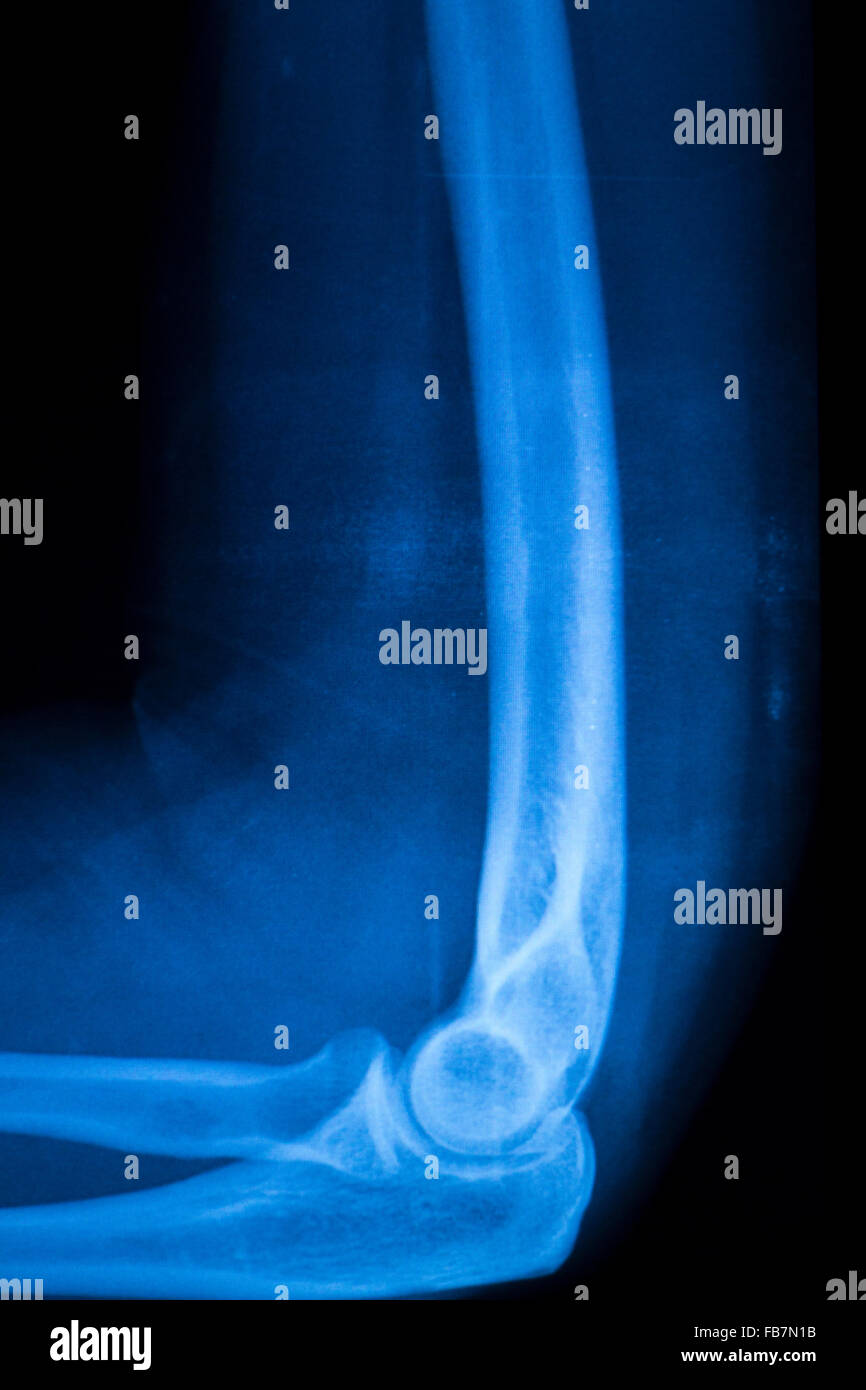

Fracture Elbow Forearm Xrays Image Showing Plate And Screw Fixation Elbow Surgery Plate And Screws The patient does not follow. elbow, putting the fracture fragments back in their normal position, and holding them there with some type of fixation. The acumed olecranon plates provide fixation for both fractures and osteotomies in the proximal ulna. The system features the hexalobe screw system with. This can occur for a number of reasons, including: this might. Elbow Surgery Plate And Screws.

From www.alamy.com